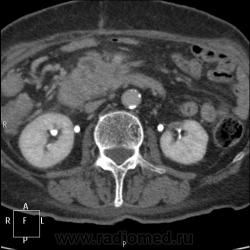

КТ поджелудочной железы. Пациентка 80 лет.

Упорные боли, кратковременно купируются ненаркотическими анальгетиками. Диастаза мочи 300. Кровь без особенностей. Псевдотуморозный панкреатит или опухоль? Опыта с панкреатитами - кот наплакал в знойный день))...

С левой почкой - кто такое видел? Атрофия средней трети и частично нижнего полюса, а в верхнем... помогите, пожалуйста!)) Вроде доброкачественное обызвествление. Не получилось напоить водой - несколько глотков и наотрез отказалась - тошнота. Поэтому 12-перстная безконтрастная практически.

На мой взгляд - опухоль головки ПЖ. Атроифя\ хоста и тела. Вирсунг расширен до зоны образования в головке - дальше четко не определяетя. Обычно при панкреатитах вирснуг хоть дефоримрованный но проходит через зону фиброзно-воспалиетльных изменений. Тут же похоже его обтурация.

На 45 секунде оразовние несколко гиподенсно по отношению к другой паренхиме (хотя и фиброз тоже такой будет).

Вообщим опухоль на мой взгляд головки ПЖ.

Согласен,кроме того,на 57-60 секундах в толще образования определяется ветвь верхней брызжеечной артерии.

А в левой почке не туберкулез ли?